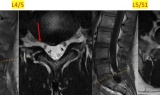

Đi khám vì đau thắt lưng, nam thanh niên 25 tuổi phát hiện hàng loạt vấn đề cơ xương khớp -